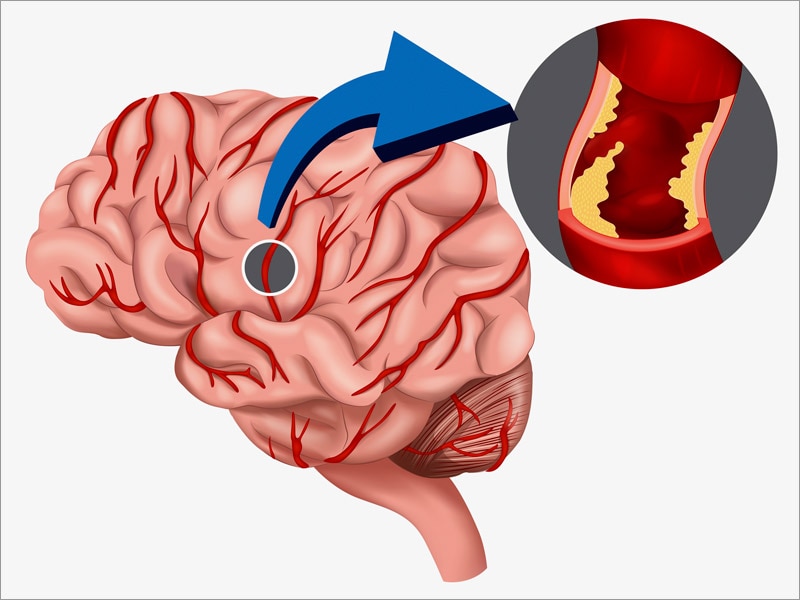

Ишемический инсульт левой стороны: симптомы и реабилитация